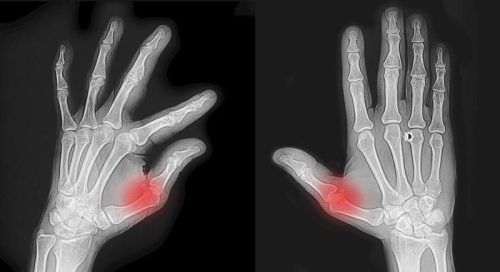

Das Daumensattelgelenk kann bei Verschleiß durch Arthrose stark schmerzen. © Smarterpix

Bei Arthrose wird der schützende Knorpel im Gelenk abgebaut. Dies führt zu Schmerzen, Steifigkeit, Schwellungen und eingeschränkter Beweglichkeit und manchmal auch geschwollenen Gelenken. Möglicherweise gibt es s